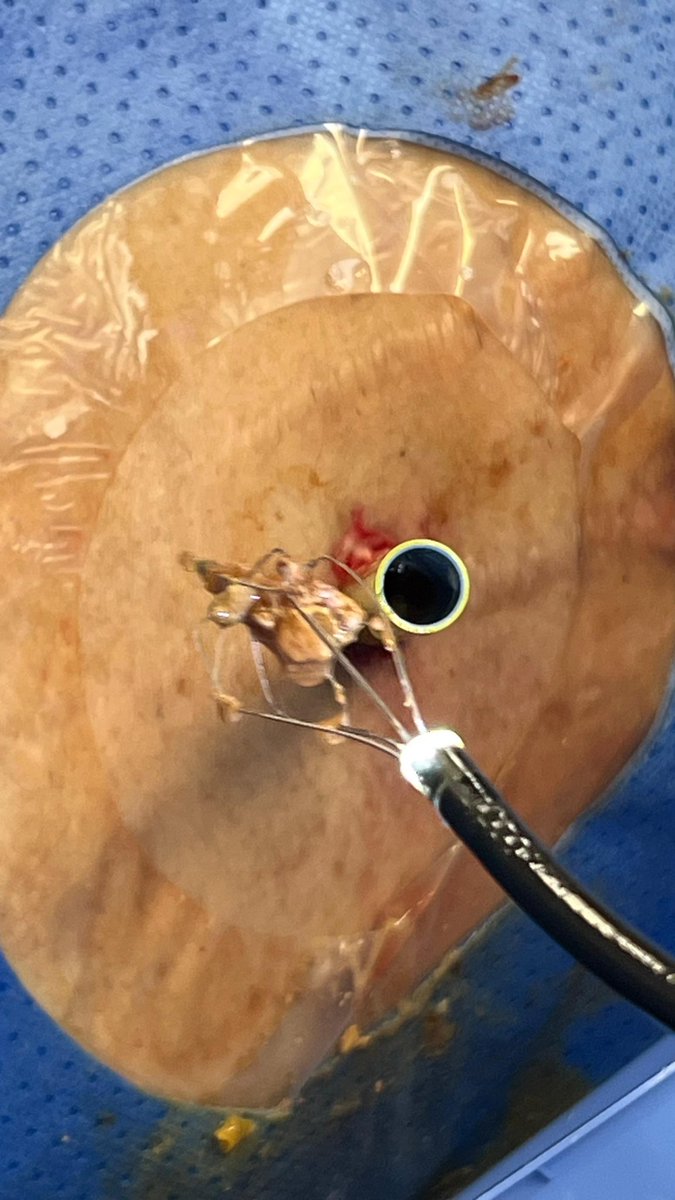

The evolving future of IR perc endoscopy; stone extraction, lithotripsy, cholecystoduodenostomy LAMS placement and removal, Necrosectomy, leaks and fistula management… #Innovation

Percutaneous Necrosectomy - Newer low-profile devices allow for deep and multi-directional tunneling to reach non-accessible areas - Equipment & accessories, from different medical specialties, can be used in a compatible fashion to achieve different goals - Image guidance keeps